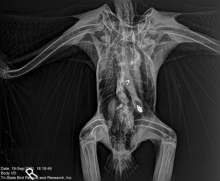

What Thanksgiving Turkey DYSGENICS OF AN INDIGENOUS SPECIES by INVASIVE NAZI Colony Slavery Holocaust looks like WASHINGTON (AP) — Researchers report harmful levels of toxic lead were found in the bones of 46% of bald eagles sampled in 38 states.

Nearly half of US bald eagles suffer lead poisoning

WASHINGTON (AP) — Researchers report harmful levels of toxic lead were found in the bones of 46% of bald eagles sampled in 38 states.